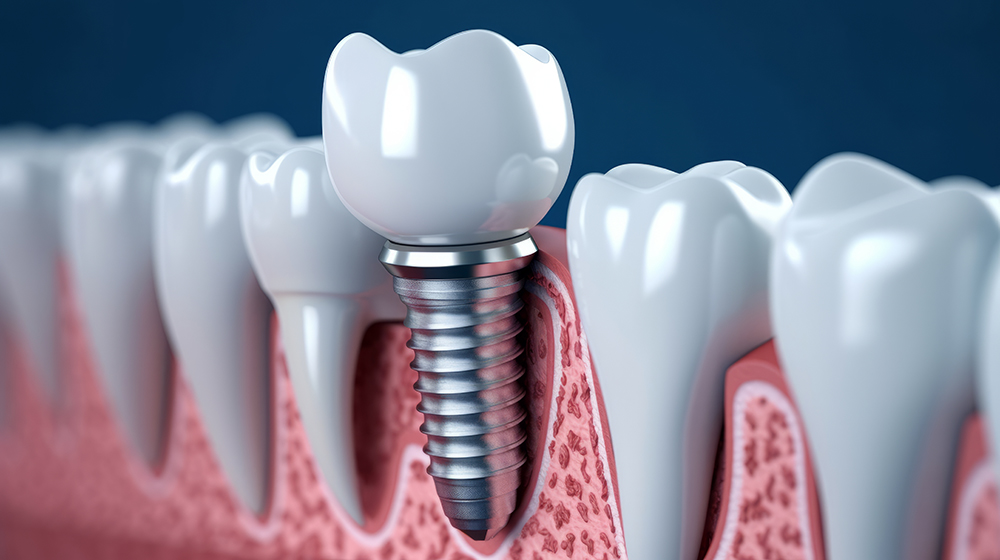

4. 골유착 기간

임플란트가 뼈와 단단히 결합하는 과정을 '골유착'이라고 부릅니다. 이 기간은 약 3개월에서 6개월이 필요하며, 뼈 상태에 따라 다를 수 있습니다. 골유착이 잘 이루어져야만 임플란트가 안정적으로 자리잡고, 정상적인 기능을 수행할 수 있습니다.

5. 지대주 및 보철물 부착

골유착이 완료되면 임플란트 위에 지대주(어버트먼트)를 연결하고, 그 위에 보철물을 부착합니다. 이 과정에서 환자 맞춤형 치아 모양을 디자인하고 제작하며, 자연치아와 최대한 유사하게 보이도록 조정합니다. 최종적으로 임플란트 보철물을 설치하며, 이로써 전체 시술이 마무리됩니다.